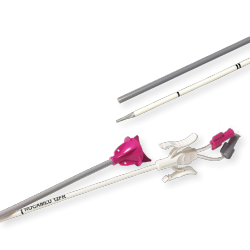

ENDOSIL® – Silicone Double Loop Ureteral Stent

Stiff Kit – With Nitinol Guide Wire